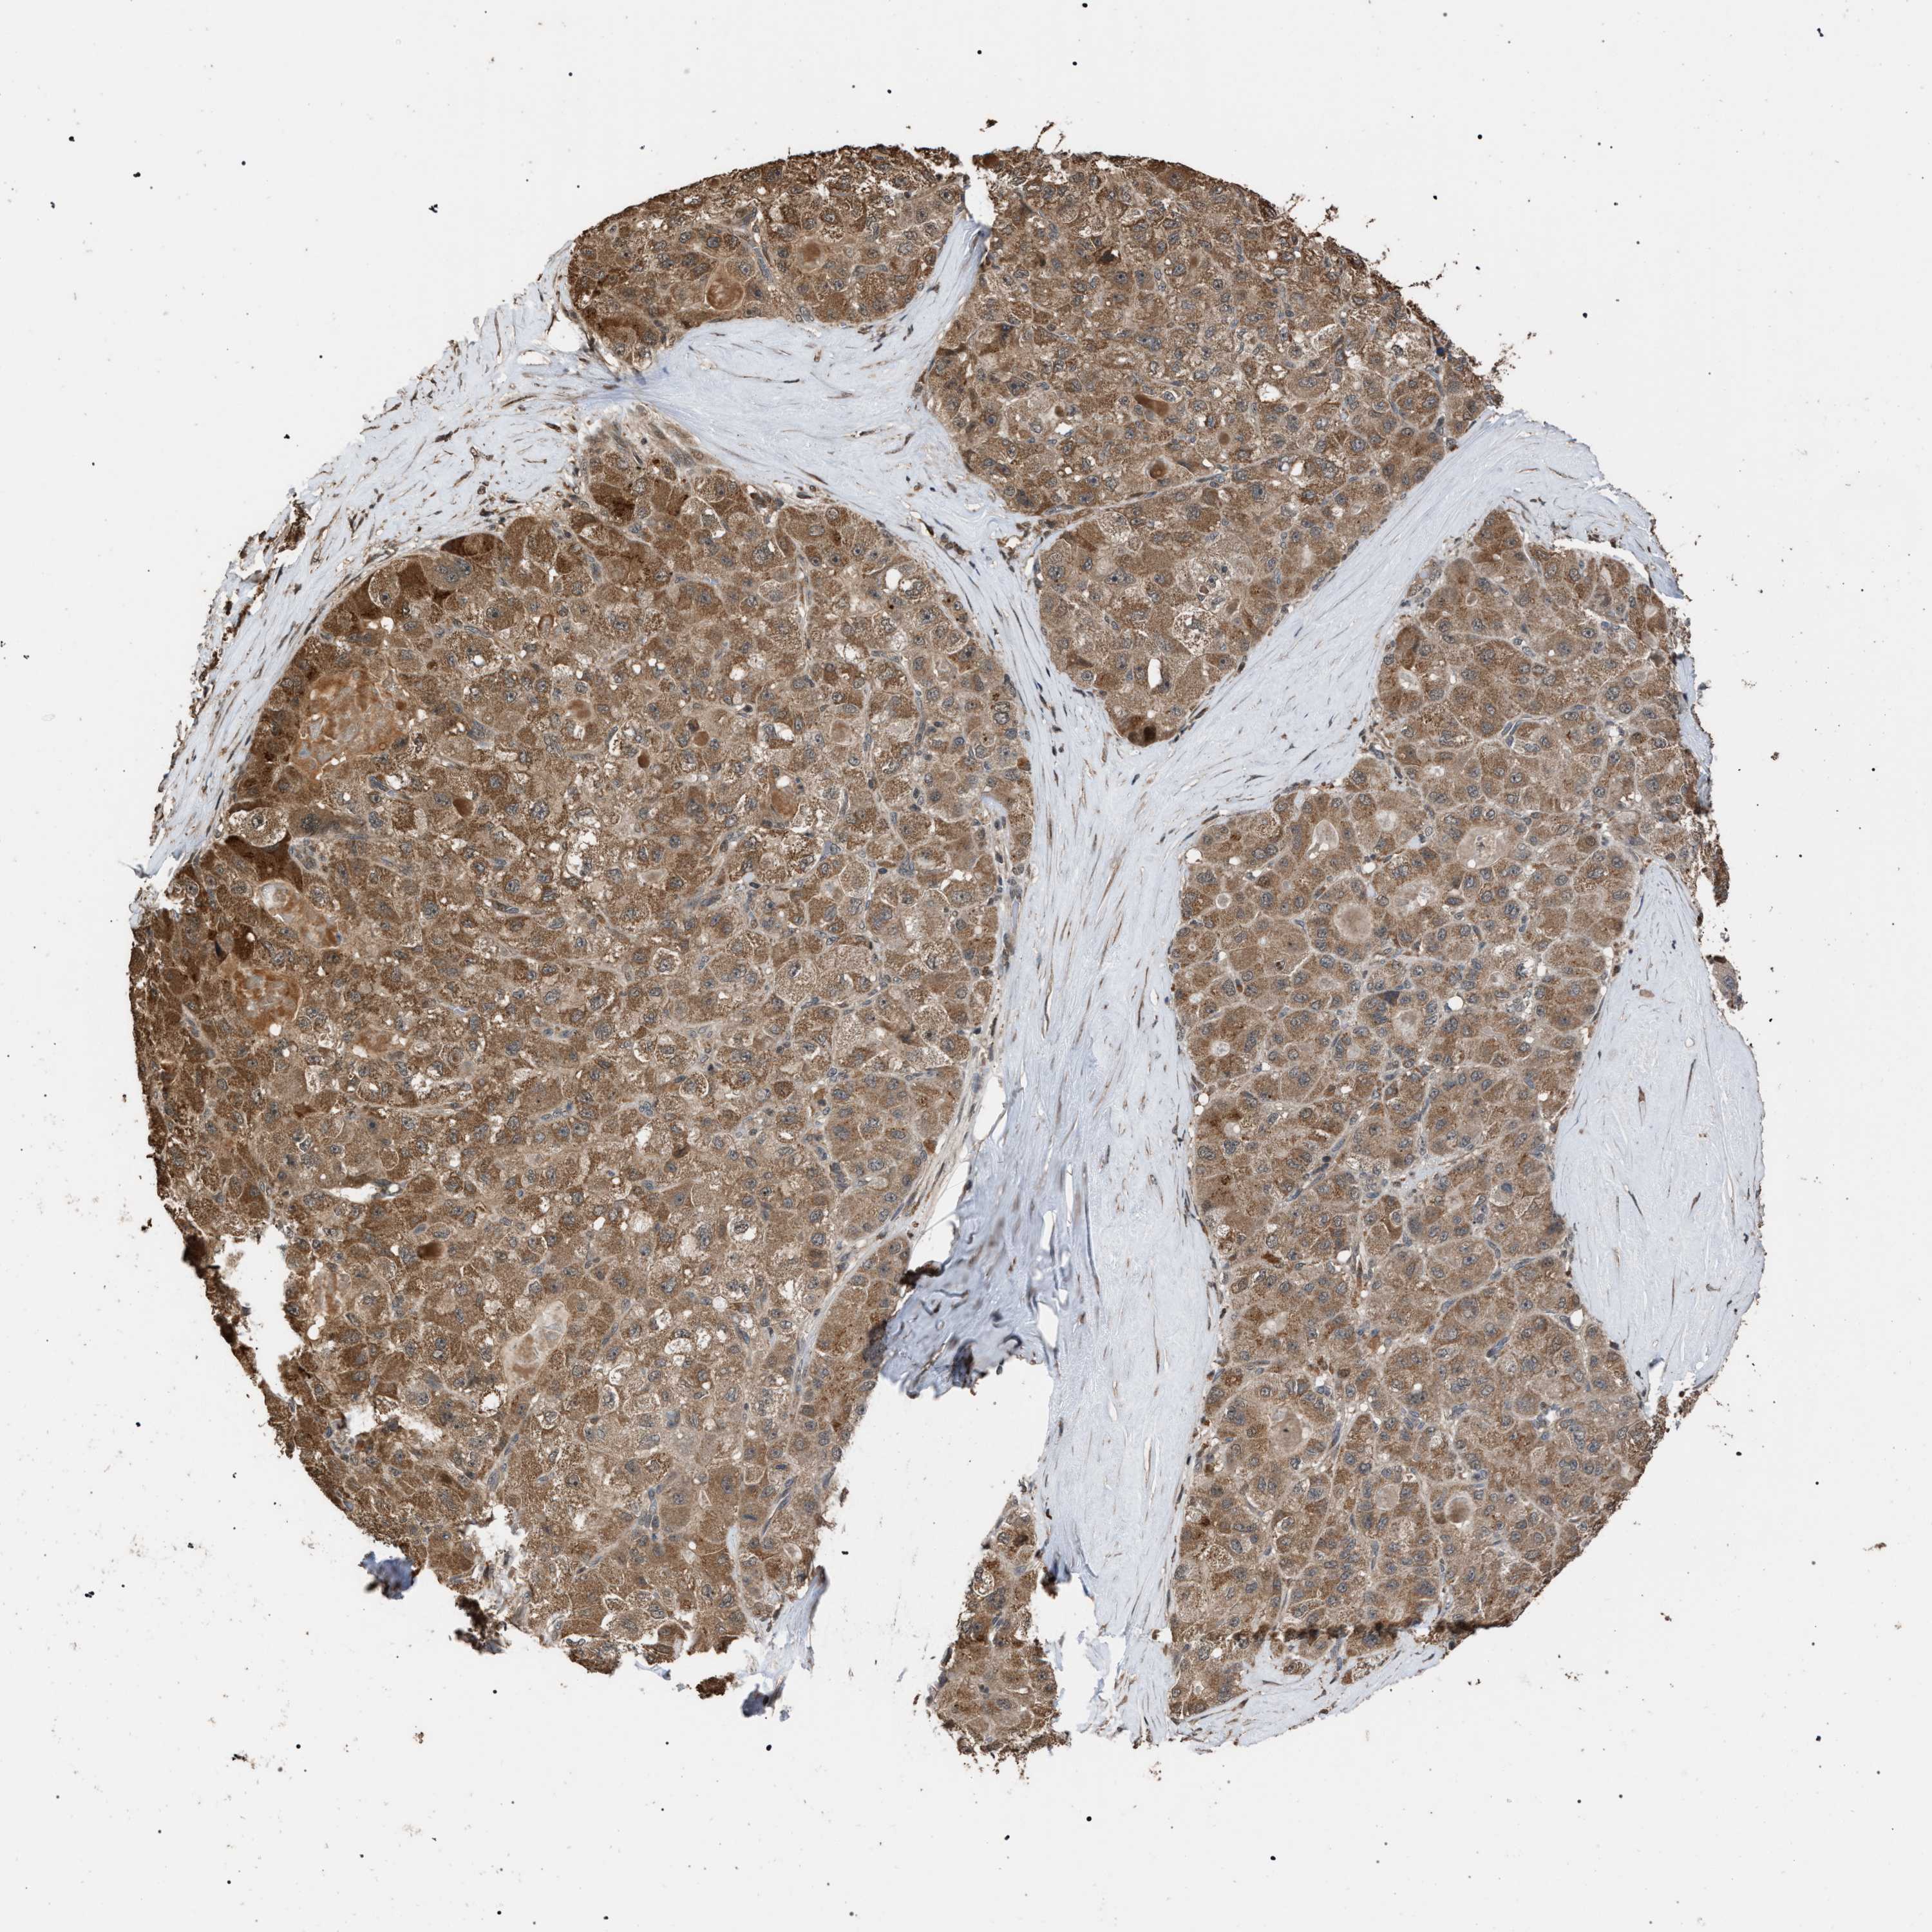

LIVER CANCER - Protein expressioni

A mouse-over function shows sample information and annotation data. Click on an image to view it in a full screen mode. Samples can be filtered based on level of antibody staining by selecting one or several of the following categories: high, medium, low and not detected. The assay and annotation is described here.

Note that samples used for immunohistochemistry by the Human Protein Atlas do not correspond to samples in the TCGA dataset.

Antibody stainingi

Antibody staining in the annotated cell types in the current human tissue is reported as not detected, low, medium, or high, based on conventional immunohistochemistry profiling in selected tissues. This score is based on the combination of the staining intensity and fraction of stained cells.

Each image is clickable and will lead to virtual microscopy that enables deeper exploration of all samples and also displays staining intensity scores, fraction scores and subcellular localization as well as patient and tissue information for each sample.

Antibody HPA021547

Staining

High

Medium

Low

Not detected

Intensity

Strong

Moderate

Weak

Negative

Quantity

>75%

75%-25%

<25%

None

Location

Nuclear

Cytoplasmic/membranous

Cytoplasmic/membranous,nuclear

Cholangiocarcinoma

Carcinoma, Hepatocellular, NOS